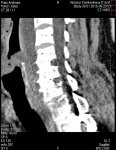

Das nennt sich Versteifung C5-6 und C6-7.